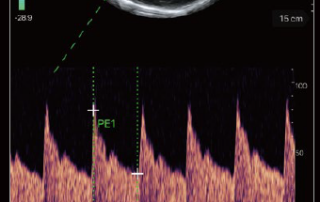

TE Air